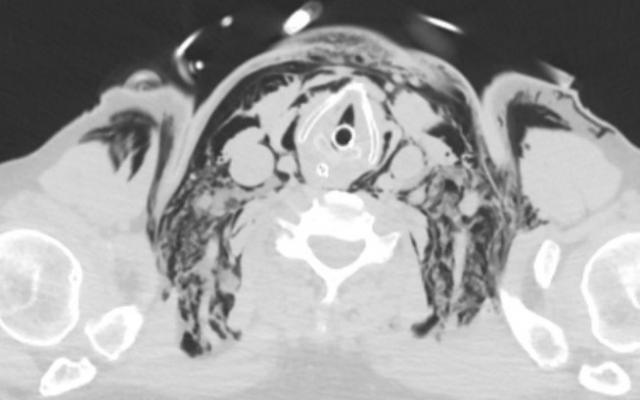

Een 65-jarige man onderging een oesofaguscardiaresectie vanwege een distaal oesofaguscarcinoom. Postoperatief was er sprake van een aanhoudende lage zuurstofsaturatie. Op de 5e dag na de operatie kreeg patiënt een nasale siliconen zuurstofsonde (CH10; diameter: 3,3 mm) in het linker neusgat. Direct nadat patiënt zuurstof 6 l/min kreeg toegediend, klaagde hij over hevige pijn aan het linker oor. In enkele minuten ontstond fors subcutaan emfyseem in de linker gelaatshelft en daarna de hals (figuur 1a). Patiënt had een inspiratoire stridor en raakte respiratoir insufficiënt, waarop hij geïntubeerd en mechanisch beademend werd. De zuurstofsuppletie via de neus werd gestopt. Binnen enkele…